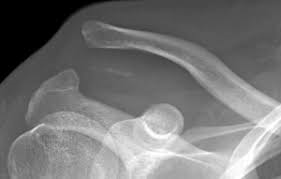

Sleutelbeen uit de kom (acromiom(sub)luxatie)

Als het sleutelbeen helemaal of gedeeltelijk uit de kom schiet, komt dat vaak door een val of klap.

Het kan zijn dat er alleen beschadiging is van het kapsel en de banden; het sleutelbeen staat nog op zijn plaats. Het kan ook voorkomen dat het sleutelbeen een klein stukje verplaatst is.

Als het gewricht helemaal uit de kom is, zijn de banden en het kapsel volledig afgescheurd. U voelt dan een hevige pijn aan de bovenkant van de schouder. Deze pijn wordt erger als op de bovenkant van het gewricht wordt gedrukt. Zijn de banden afgescheurd, dan kan het sleutelbeen in een vreemde stand staan. Er kan een zwelling en een bloeduitstorting te zien zijn. Het lukt niet goed om de schouder te bewegen. De pijn wordt erger als u uw arm laat afhangen. Waarschijnlijk heeft u daarom de neiging om uw arm te ondersteunen.